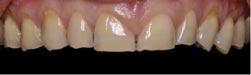

1. What injury can be diagnosed from the teledentistry photo (below), and what is the importance of timely surgery attendance for this type of injury?